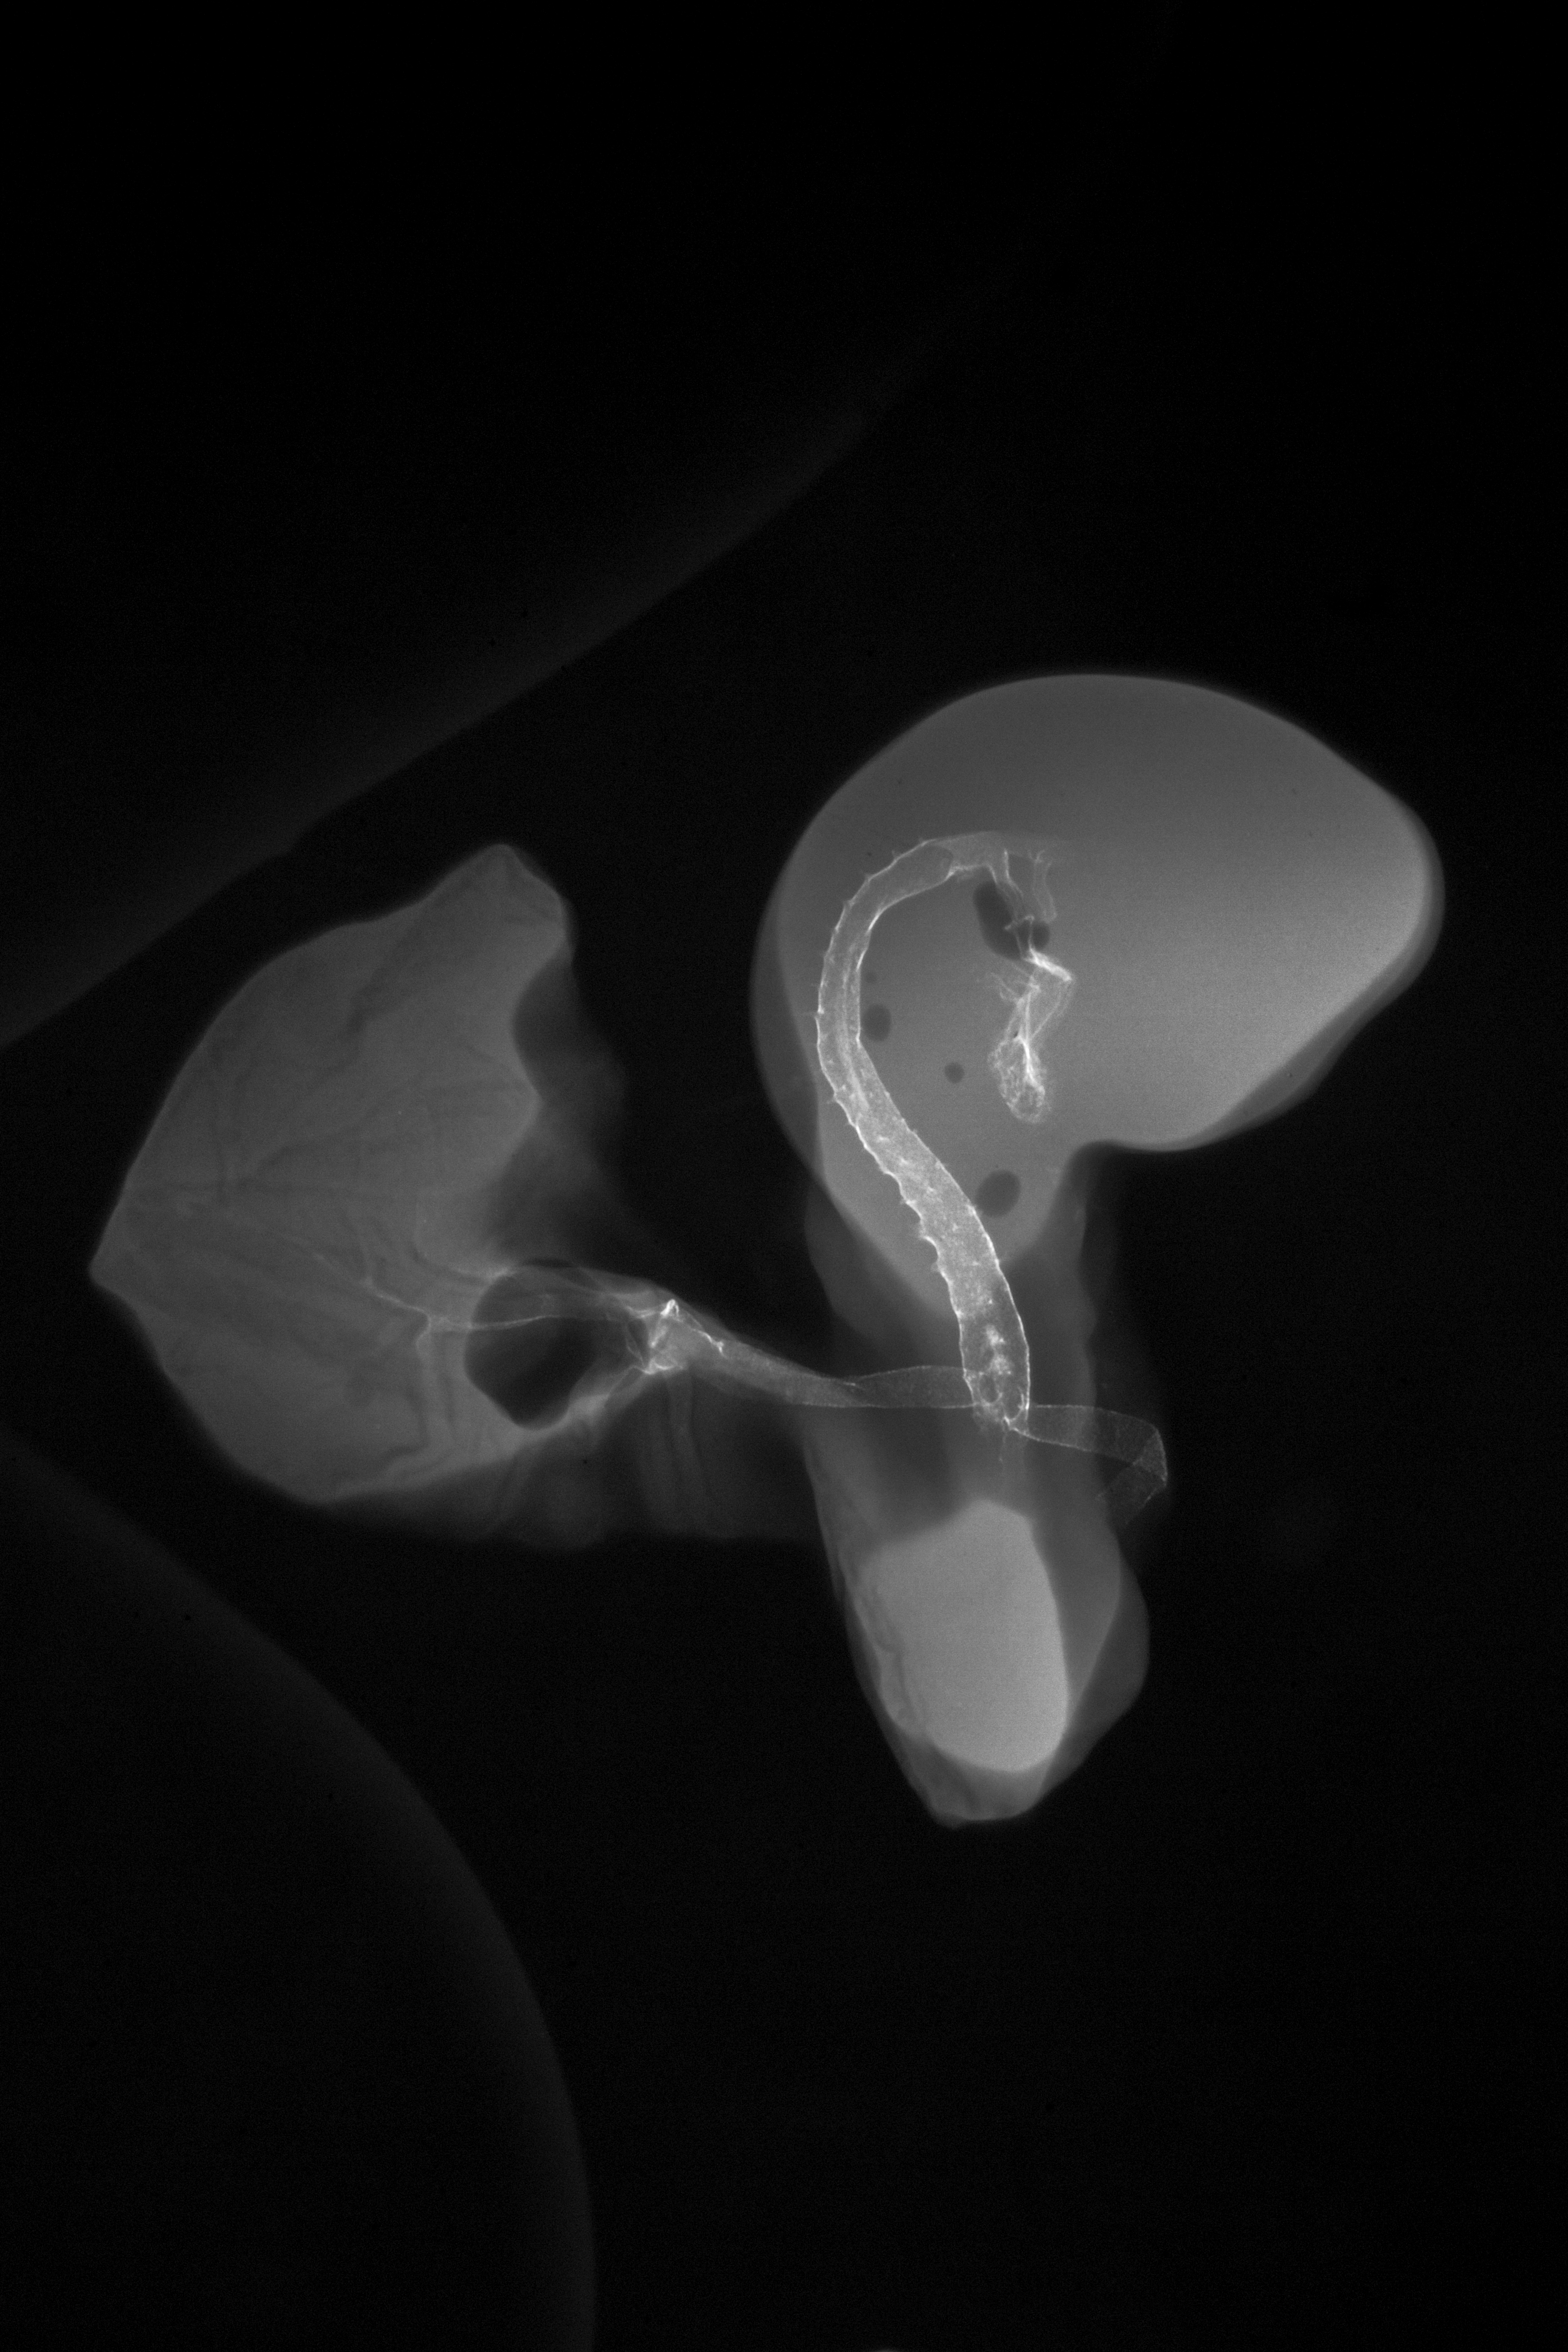

Chick Embryo Microangiography

Hamburger-Hamilton (HH) Stage 19 (approx. 3 - 3.5 days)

X-Ray Micrographs